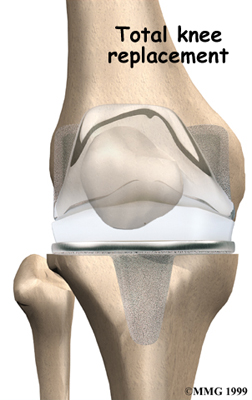

Artificial Knee Replacement

An artificial knee replacement is the ultimate solution for advanced knee OA.

Surgeons prefer not to put a new knee joint in patients younger than 60. This is because younger patients are generally more active and might put too much stress on the joint, causing it to loosen or even crack. A revision surgery to replace a damaged prosthesis is harder to do, has more possible complications, and is usually less successful than a first-time joint replacement surgery.

Related Document: FYZICAL Vienna's Guide to Artificial Joint Replacement of the Knee